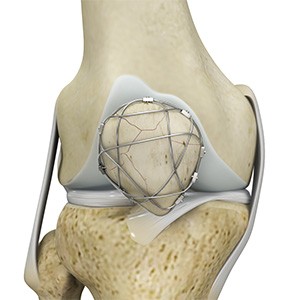

Meniscus Collagen Implant

A meniscus collagen implant is a biocompatible scaffold that is made of highly purified collagen which helps to reinforce a damaged knee meniscus and promote the growth of new tissue. The implant has the same shape as the human meniscus and can be trimmed by the surgeon to fit the size of the defect in the damaged meniscus.